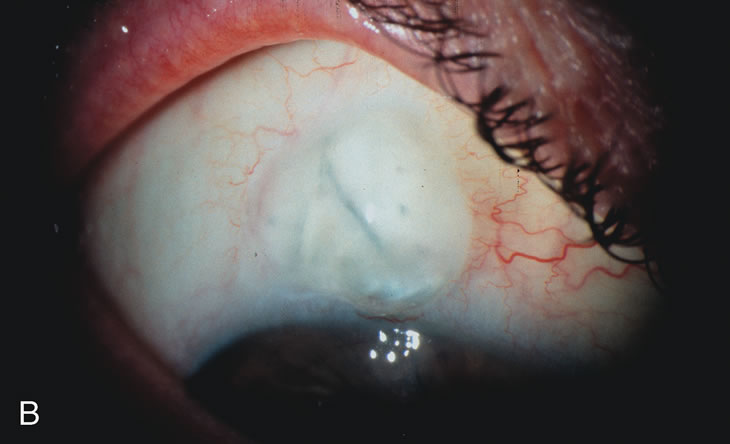

Long-term IOP control after combined cataract-glaucoma surgery is better than cataract extraction alone. Combining a cataract extraction with a filtration procedure without using an antimetabolite, results in a long-term lowering of IOP slightly greater than that caused by cataract extraction alone.83–87 Long-term IOP control after phacotrabeculectomy is better than with ECCE-trabeculectomy, with fewer medications needed in the phacotrabeculectomy group.88 5-Fluorouracil (5-FU) does not improve the IOP-lowering effect of combined cataract and glaucoma surgery. Adjunctive use of 5-FU at the time of cataract extraction has, in the dosage and methods so far used, not appreciably improved the long-term pressure lowering associated with ECCE combined with a guarded filtration procedure.89–91 There also appears to be limited pressure-lowering benefit from postoperative 5-FU injections for combined same-site phacotrabeculectomy.92–94 There is limited data on the efficacy of intraoperative 5-FU for combined phacotrabeculectomy. Mitomycin-C (MMC) does improve the IOP-lowering effect of combined cataract and glaucoma surgery. Antimetabolite usage is worth the long-term risks of blebitis and hypotony in patients who are likely to go blind without its application. However, patients without advanced disc damage who can tolerate one or two postoperative glaucoma medications may not need an antimetabolite and certainly should not be exposed to high concentrations of MMC. Combined same-site phacotrabeculectomy with MMC lowers IOP more effectively with fewer postoperative medications and larger filtration blebs than without MMC.95–97 MMC also improves the success rate in blacks, eyes of patients on two or more glaucoma medications, eyes with IOP 20 mm Hg or higher, and prior failed trabeculectomy.98,99 Antimetabolite use in combined procedures is associated with a lower postoperative IOP with reduced need for long-term glaucoma medications.100 MMC appears to have a beneficial effect on long-term filtration surgery and on combined surgery without the corneal toxicity of 5-FU.101 However, long-term bleb morphology with MMC is different from that with 5-FU. Excessive concentrations or durations of MMC cause progressive conjunctival necrosis with bleb leaks, hypotony, and possible endophthalmitis. Antimetabolite usage has decreased with trabeculectomy surgery and is reserved for high-risk patients likely to scar down without its usage. COMBINED CATARACT AND GLAUCOMA SURGERY Phacotrabeculectomy is more effective than ECCE-trabeculectomy with or without postoperative 5-FU injections.102–105 The smaller incision associated with phacoemulsification likely leads to less intraocular inflammation and wound healing, allowing better bleb formation. Phacotrabeculectomy with intraoperative or postoperative 5-FU significantly lowers IOP but not as successfully as 5-FU trabeculectomy alone.106 This is probably related to the prolonged anterior chamber flare following phacoemulsification compared with trabeculectomy with peripheral iridectomy.107 Combined same-site phacoemulsification, posterior chamber IOL, and trabeculectomy without antimetabolite significantly lowers IOP.108–111 Results of same-site phacotrabeculectomy appear similar with either a 3.5-mm incision with a foldable IOL or a 5.2-mm incision with a rigid single piece PMMA lens.112,113 Phacotrabeculectomy with intraoperative 5-FU is as efficacious as a 5-FU trabeculectomy followed by phacoemulsification.114 Visual acuity and complications of combined phacotrabeculectomy are comparable to a two-staged approach with the obvious benefit of earlier visual rehabilitation.115 Foldable silicone lenses are associated with an increase in postoperative inflammation compared to PMMA lenses.116 SINGLE-SITE VERSUS TWO-SITE COMBINED CATARACT AND GLAUCOMA SURGERY Combined ECCE-trabeculectomy techniques now yield to smaller incision combined phacotrabeculectomy. The methods for combining phacotrabeculectomy vary, depending on physician training, preference and patient anatomy. For example, physicians with two-site experience will have an easier access to the surgical site in a patient with enophthalmos and a prominent brow who requires a combined procedure. A temporal approach for the lens extraction is much easier in this particular case. IOP control following one-site versus two-site phacotrabeculectomy with MMC is similar but with a trend for less postoperative glaucoma medications,117 improved IOP control,118 less induced astigmatism,119 and better bleb formation in the two-site group.120 CATARACT EXTRACTION CAUSES PARTIAL OR COMPLETE FAILURE OF EXISTING FILTERING BLEBS Cataract extraction by any technique performed in a patient with a pre-existing filter will have an effect on the previous filtering bleb.121–124 Bleb failure is more likely with ECCE compared with small-incision phacoemulsification.125 However, even patients undergoing topical anesthesia with clear corneal phacoemulsification and foldable IOL may experience bleb failure. One of three patients with a functioning filter and preoperative mean IOP of 12 mm Hg without antiglaucoma medications experiences bleb failure after lens extraction (Table 2). These patients require long-term drug therapy or bleb needling to control IOP. 126 Additional incisional glaucoma surgery may eventually be required in up to 10% of patients.127 Intraoperative iris manipulation may cause significant breakdown of the blood–aqueous barrier, resulting in inflammation that causes bleb failure. Even after uncomplicated clear corneal phacoemulsification, IOP may increase an average of 2 to 3 mm Hg due to bleb fibrosis.128 Approximately 20% of filtered patients require a long-term increase in glaucoma medications following uncomplicated clear corneal phacoemulsification with a foldable copolymer acrylic IOL129 (Fig. 3). In situations in which the bleb is not working at all, the eye will have a postoperative pressure spike that mimics that in the patient not having had a prior filtering procedure. In situations in which the bleb is marginal, the pressure spikes tend to be lower, and the final postoperative IOP tends to be around 50% higher than it was preoperatively. These patients require combined procedures in order to reestablish long-term filtration. In situations in which the bleb is very thin, polycystic, and associated with an IOP around 5 to 8 mm Hg on no antiglaucoma therapy; uncomplicated cataract extraction will have a minimal effect on the level of IOP. Patients with functioning glaucoma drainage implants usually have minimal long-term changes in IOP after uncomplicated cataract extraction.130

| CASE 5: ANTICIPATED LENS EXTRACTION POST SUCCESSFUL TRABECULECTOMY | |

A patient with long-standing primary open-angle glaucoma

with a successful glaucoma filtration procedure and IOP of 10 mm Hg on

no antiglaucoma medications develops a significant, moderately dense

nuclear sclerotic cataract. This patient is best served by small incision

cataract extraction with foldable IOL implantation. Less desirable

options include ECCE with IOL implant via clear cornea, temporal limbus, or

inferior approach. Astigmatism, wound instability, prolonged visual

recovery, visual fluctuation, exposed sutures, and bleb failure are

the major drawbacks to large-incision lens extraction. Even

after the surgeon has mastered large-incision clear corneal cataract

extraction, long-term wound shift and astigmatism are a chronic

problem (Fig. 6). Inferior cataract extraction is difficult for those not experienced

with it. With the advent of small-incision phacoemulsification

surgery, the surgeon is now able to use a limbus approach adjacent

to the bleb or a clear corneal temporal approach. Postoperative inflammation

is less with the smaller incision, and filtering blebs are more

likely to survive. Patients with IOP greater than 10 mm Hg after a

filtering procedure are more likely to experience permanent IOP elevation

after phacoemulsification. Patients should understand that IOP elevation

post cataract extraction is always an issue, even with a functioning

filter.